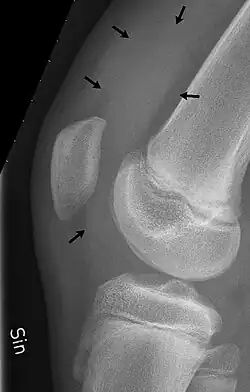

As bursas do joelho são sacos cheios de líquido e bolsas sinoviais que circundam a cavidade da articulação do joelho. As bursas têm paredes finas e são preenchidas com líquido sinovial . Eles representam o ponto fraco da articulação, mas também fornecem ampliações para o espaço articular.[1] Elas podem ser agrupadas em bursas comunicantes e não comunicantes ou, conforme sua localização - frontal, lateral ou medial.

Na parte da frente do joelho existem cinco bursas:

- a bursa suprapatelar ou recesso entre a superfície anterior da parte inferior do fêmur e a superfície profunda do quadríceps femoral.[2] Ela permite o movimento do tendão do quadríceps sobre a extremidade distal do fêmur. Em cerca de 85% dos indivíduos, essa bursa se comunica com a articulação do joelho. A distensão desta bursa é geralmente uma indicação de derrame no joelho .[3]